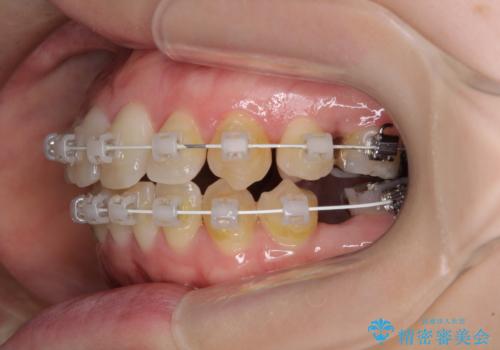

- 矯正装置

- 審美装置

イレギュラーな大臼歯抜歯矯正であったため、治療期間の長期化が想定されましたが、何とか3年ちょうどで終えることができました。

今後は目立っている銀歯を中心にセラミッククラウンなどへ交換していく予定です。